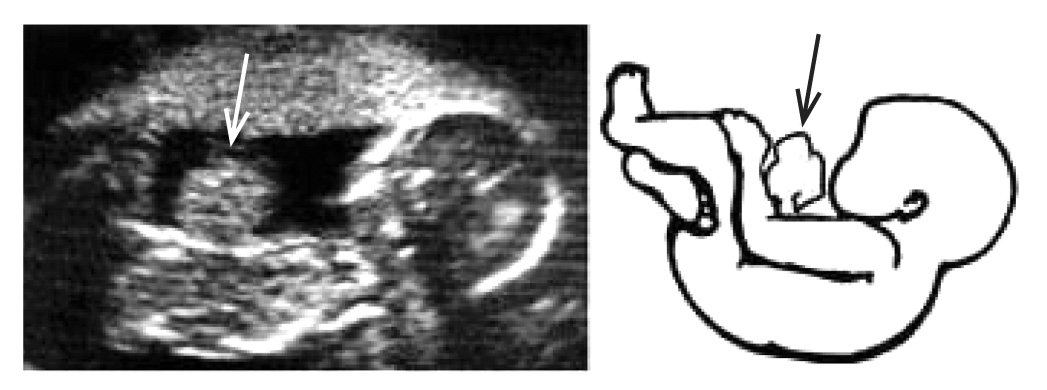

По данным медицинской карты стационарного больного К., 22.05.2018 г. р., новорождённая поступила в отделение реанимации КОГБУЗ «Кировская областная детская клиническая больница» (далее КОДКБ) 22.05.2018 с диагнозом «Врождённый порок развития: высокая кишечная непроходимость». Из анамнеза известно, что ребёнок от 2-й беременности, осложнённой врождённым пороком развития плода (обструкция кишечника). Роды первые, на 33-й нед, плановое кесарево сечение. Длительность безводного периода более 3 сут. Оценка по шкале Апгар 7/8 баллов. Масса тела 2700 г, длина 47 см, окружность головы 32 см, окружность груди 30 см. 25.10.2017 мать встала на учёт по беременности на сроке 4–5 нед. На сроке 10–12 нед было проведено первое ультразвуковое исследование (УЗИ), у ребёнка выявлена врождённая патология — гастрошизис. Прервать беременность мать отказалась (рис. 2).

Рис. 2. Антенатальное ультразвуковое исследование плода с гастрошизисом и визуализационная схема порока (стрелкой обозначен экстраперитонеально расположенный кишечник)

Второе УЗИ плода было проведено на 20-й нед, по результатам обследования диагноз гастрошизиса был исключён, однако была выявлена врождённая патология — расширенные петли кишечника в верхних отделах брюшной полости. Очередное УЗИ было проведено на 32-й нед: подтверждена обструктивная патология кишечника. 17.05.2018 — предродовая госпитализация в КОГБУЗ «Кировский перинатальный клинико-диагностический центр».